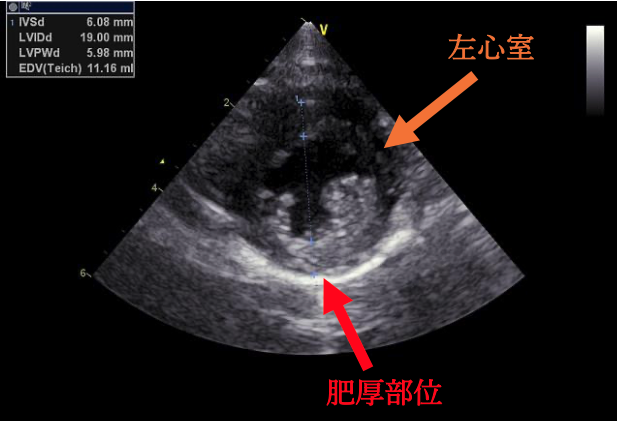

今回の心臓超音波検査では、左心室の壁が厚くなり、大動脈に血液を送り出す出口が少し狭くなっていることが確認されました。ただし、ねこちゃんには症状がなく、検査上でも重度ではなかったため、今回はお薬を使わずに経過観察となりました。

肥大型心筋症とは、左心室の壁が厚くなってしまい、血液をうまく送り出せなくなる病気です。